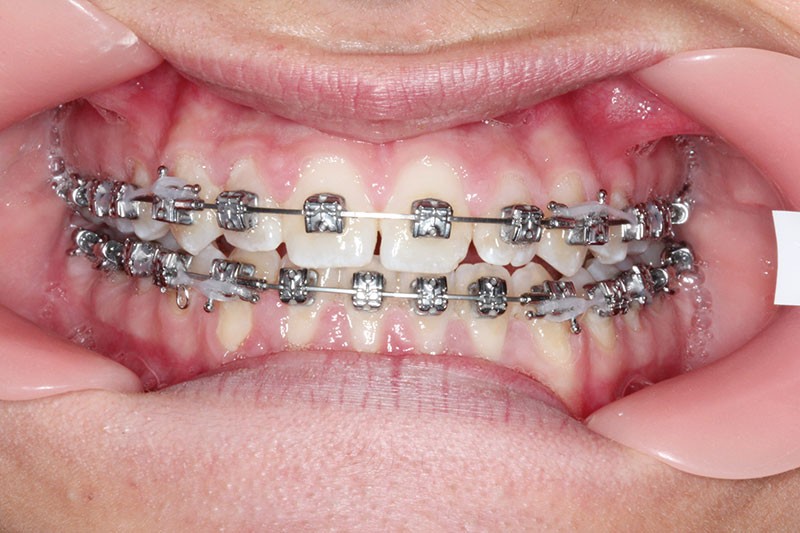

1re phase : recul des secteurs latéraux mandibulaires avec le Motion Classe III Carriere (fig. 4 à 6)

Nous mettons en place des bras latéraux Motion associés à des élastiques intermaxillaires ancrés sur des brackets sur 17 et 27 et une gouttière thermoformée maxillaire portée jour et nuit :

• 1er mois : élastiques 6 oz. 1/4”

• 2e mois et suivants : élastiques 6 oz.1/4“

L’objectif de cette étape est d’obtenir un recul des secteurs latéraux mandibulaires afin de positionner les molaires et canines en classe I et de réorienter le plan d’occlusion en haut en avant.